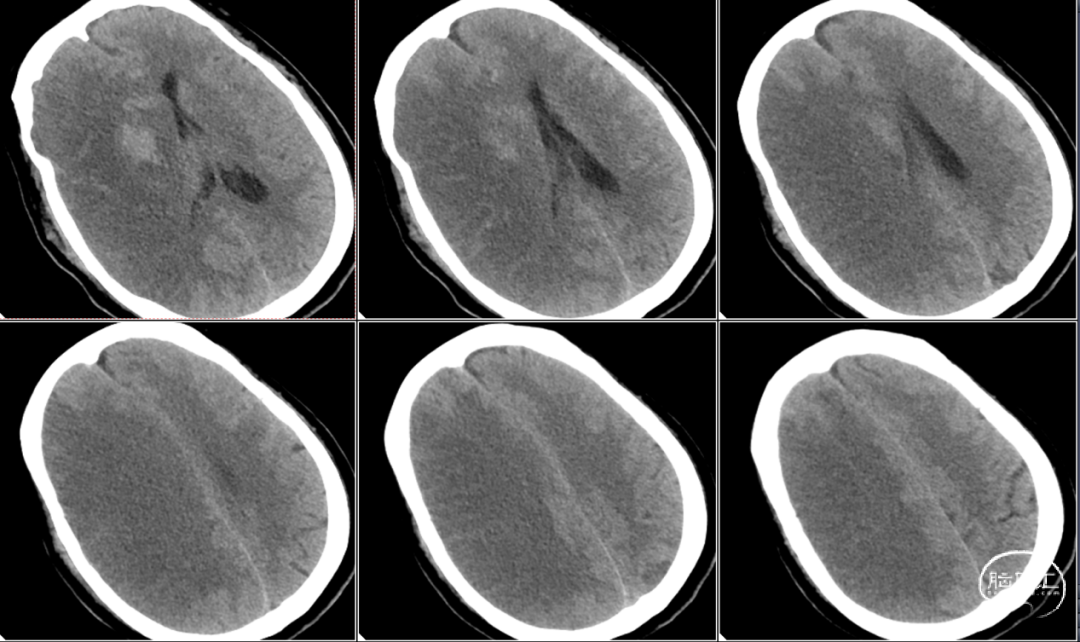

术后即刻CT提示可见造影剂外渗,未见明显脑水肿。

术后24小时复查CT提示脑水肿明显。查体神志中昏迷,双侧瞳孔不等大,右侧4mm,左侧2mm,光反应迟钝。无肢体抽搐,无恶心呕吐。